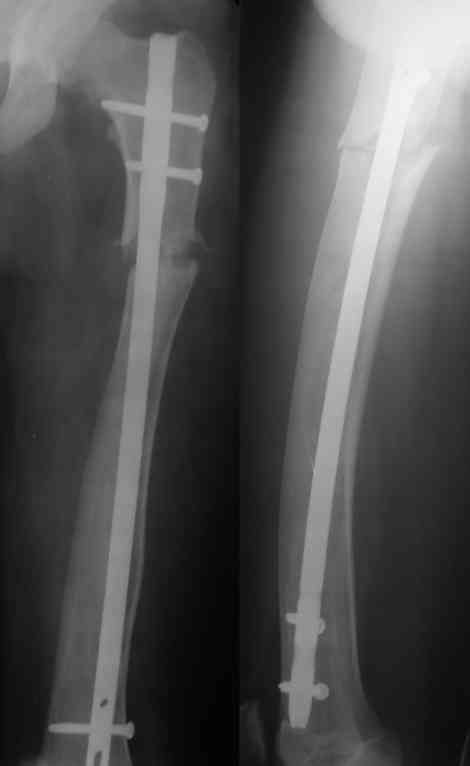

У нас был "похожий случай" патологический перелом деформированного бедра у подростка на фоне нейрофиброматоза, заштифтовали с небольшими трудностями.